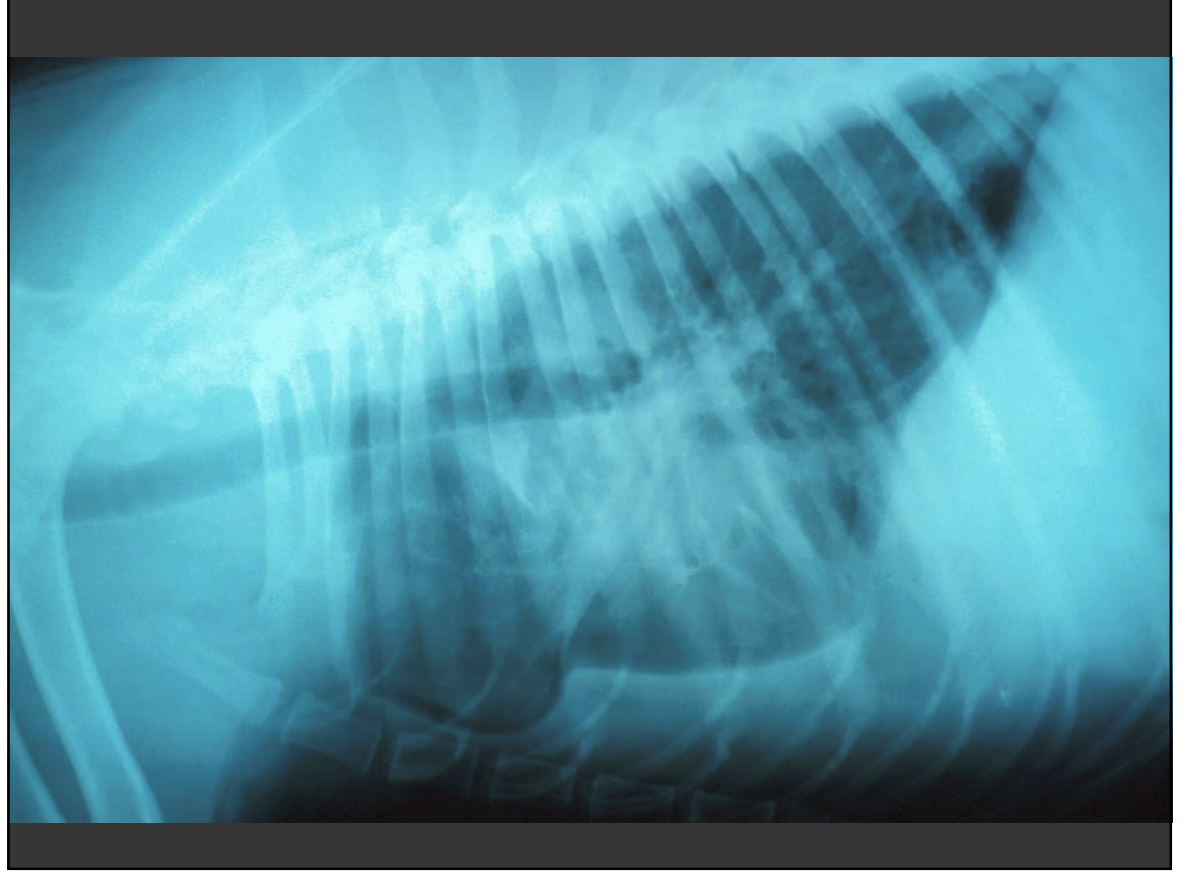

chest xray in canine lymphoma

Lat and DV sufficient

• Lymph node enlargement – cranial mediastinal, suprasternal, tracheobronchial nodes and thymus

• Pulmonary infiltration – variable appearance, difficult to differentiate from age change – micronodular interstitial pattern

• Pleural effusion

• consider comorbidity

<p>Lat and DV sufficient </p><ul><li><p>Lymph node enlargement – cranial mediastinal, suprasternal, tracheobronchial nodes and thymus </p></li><li><p>Pulmonary infiltration – variable appearance, difficult to differentiate from age change – micronodular interstitial pattern </p></li><li><p>Pleural effusion </p></li><li><p>consider comorbidity</p></li></ul><p></p>